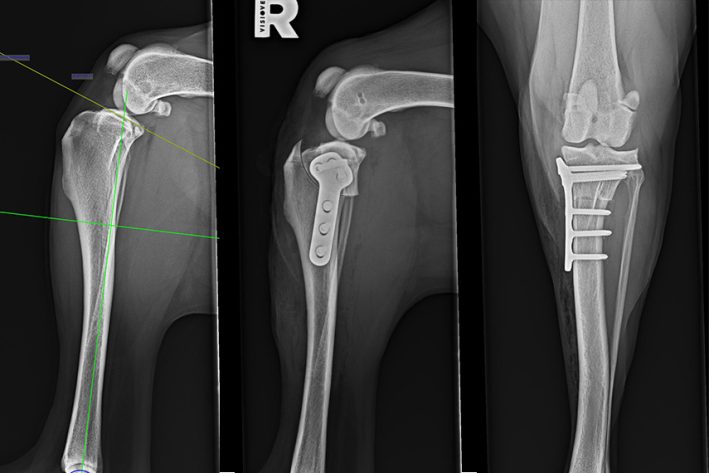

Vermessung der Kniegelenke vor und nach einer TPLO Operation

Bild 1: Vermessung des Tibiaplateauwinkels. Bild 2: Röntgen mit Implantat post-OP, laterale Ansicht. Bild 3: Röntgen mit Implantat post-OP, craniocaudale Ansicht